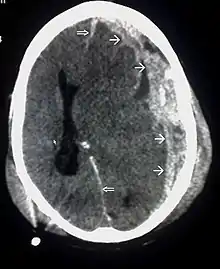

Movement disorders that may develop after TBI include tremor, ataxia (uncoordinated muscle movements), spasticity (muscle contractions are overactive), myoclonus (shock-like contractions of muscles), and loss of movement range and control (in particular with a loss of movement repertoire).[89][147] The risk of post-traumatic seizures increases with severity of trauma (image at right) and is particularly elevated with certain types of brain trauma such as cerebral contusions or hematomas.[138] People with early seizures, those occurring within a week of injury, have an increased risk of post-traumatic epilepsy (recurrent seizures occurring more than a week after the initial trauma).[148] People may lose or experience altered vision, hearing, or smell.[11]